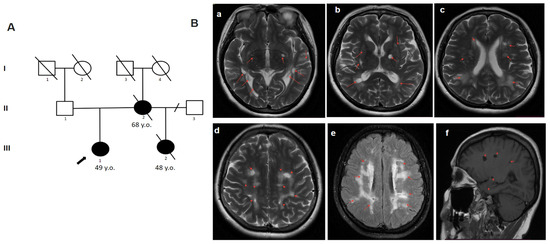

2.4.4. Patient 4.1

2.4.3. Patient 3

2.4.2. Patient 2

2.4.1. Patient 1